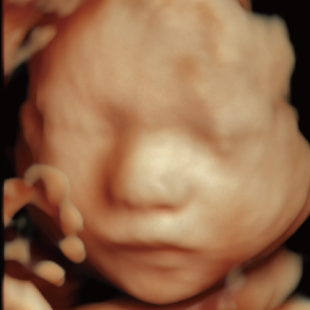

妊娠中期になると、胎児の体や内臓の構造がよりはっきりと確認できるようになります。 中期スクリーニングでは、頭部、顔面、頸部、胸部、腹部、心臓、手足、外性器、臍帯や胎盤など、全身をくまなく観察し、形態の状態を詳しく確認します。この頃に染色体数の変化を疑わせる所見が確認される事もあります。

胎児ドックの様子_中期_頭 胎児ドックの様子_中期_顔面 胎児ドックの様子_中期_心臓 胎児ドックの様子_中期_腹部 胎児ドックの様子_中期_足 胎児ドックの様子_中期_4D